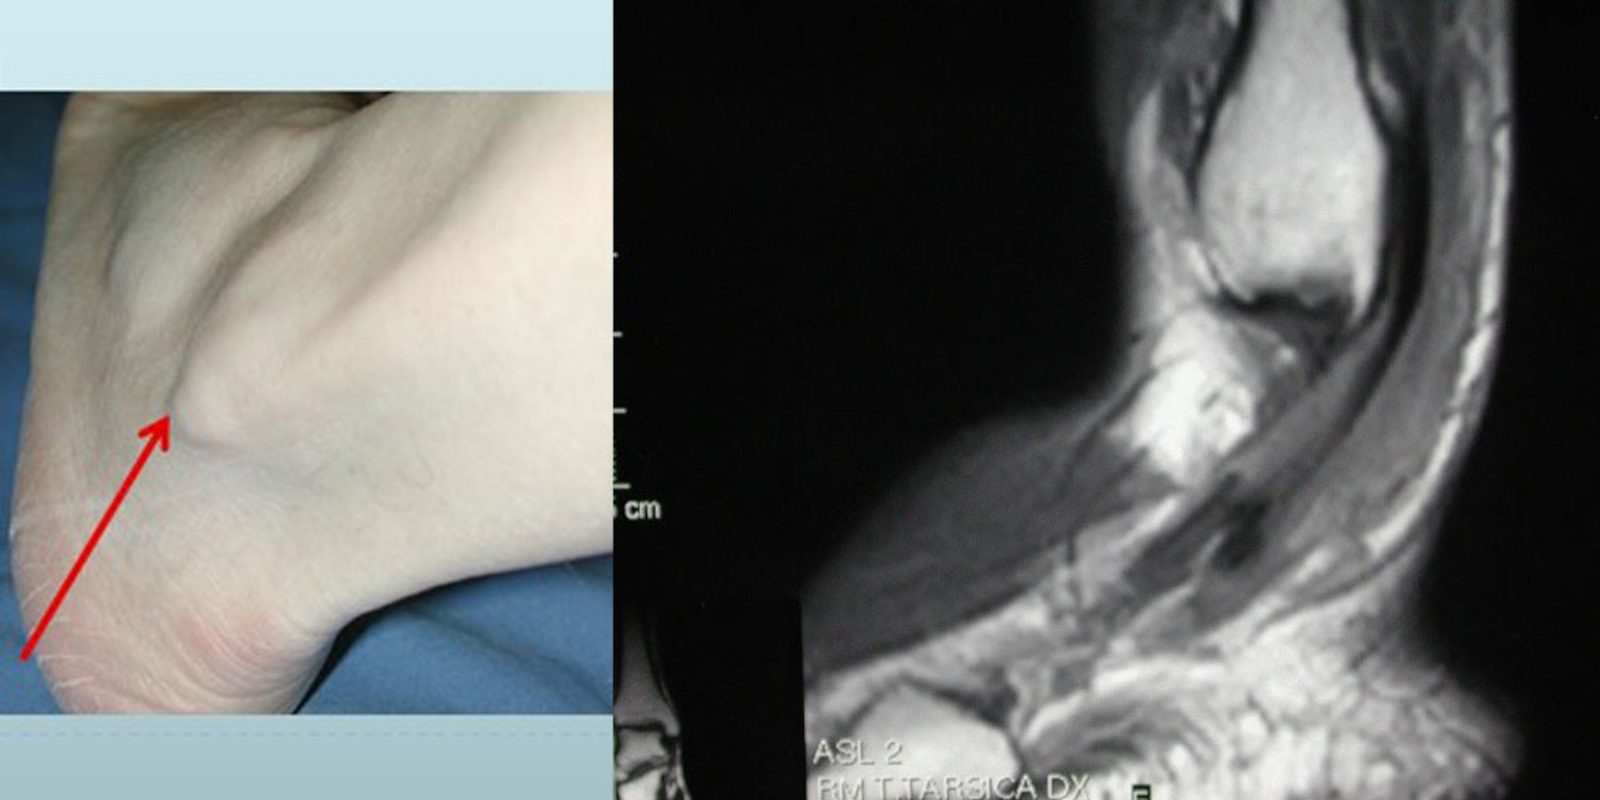

L’esame ecografico permette una soddisfacente indagine dello stato dei tendini, mentre la risonanza magnetica permette di valutare lo stato cartilagineo e dei legamenti.

La tendinite dei peronei della caviglia è caratterizzata da dolore localizzato nella parte esterna e posteriore della caviglia, soprattutto quando si ruota la caviglia verso l’interno. Il dolore è accompagnato da gonfiore, da un lieve bruciore nella parte laterale del piede e da una certa debolezza quando si ruota la caviglia verso l’esterno.

Il trattamento chirurgico della tendinite dei peronei viene preso in considerazione solo in caso di lesioni importanti: rottura del tendine o lussazione cronica dei peronei associata ad una tenosinovite.